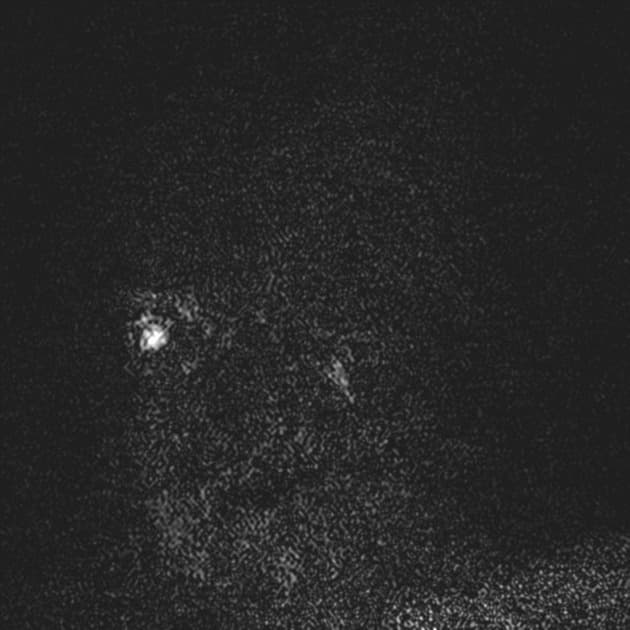

- Các tổn thương rải rác, dạng vệt hoặc hình tròn, tăng tín hiệu trên hình ảnh khuếch tán (diffusion-weighted imaging), khu trú chủ yếu ở vùng chất trắng quanh thất (periventricular white matter), chất trắng ở bán nguyệt (juxtacortical white matter), thân gai thị – giao thoa thị giác (optic radiation – optic chiasm), và thân não (brainstem) – phù hợp với đặc điểm của xơ cứng rải rác (multiple sclerosis).

- Không có bằng chứng của phù độc tế bào (cytotoxic edema) cấp tính hay hạn chế khuếch tán (restricted diffusion) mới.